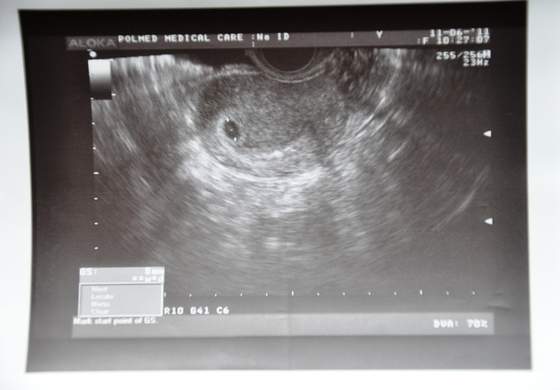

może któraś z Was wie bo ja się już doczekać nie mogę kolejnej wizyty jeżeli w5tyg 2dni (co było równy tydzień temu) było widać u mnie 8mm pęcherzyk to zakładając prawidłowy rozwój kiedy powinnam zobaczyc zarodek i bijące serduszko?? mam planowana wizyte na 25.06 ale chyba nie wytrzymam kolejnego tygodnia...

strasznie mnie to niecierpliwi ale z drugiej strony oszczędzi nerwów czy zarodek dobrze się rozwija. Ostatnio prawdopodobnie miałam puste jajo i widziałam tylko sam pęcherzyk... dlatego teraz cieszę się ze zobaczę już bąbelka! - Znaczy mam nadzieje ;-)